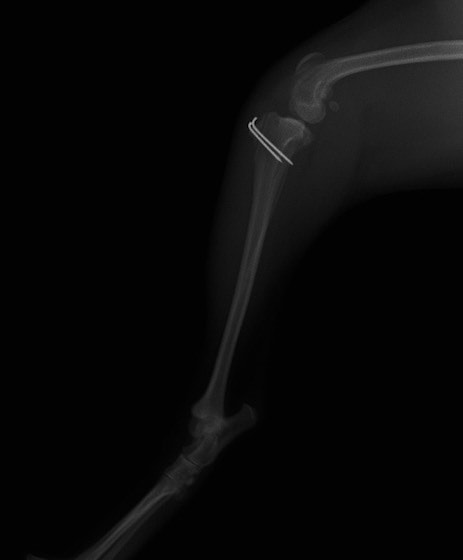

■ 症例22 ポメラニアン 1歳5か月 去勢雄

左後肢の挙上を主訴に来院した。整形学的検査、レントゲン検査より左右の膝蓋骨脱臼(左GradeⅡ〜Ⅲ、右Grade Ⅱ)を認めた。また、脛骨の前方引き出し試験の際に、引き出し兆候は認められないものの、疼痛が認められたため、前十字靭帯の損傷が疑われた。術中における、目視および関節内の操作によって、前十字靭帯の損傷や過伸展といった異常が認められなかったため、膝蓋骨脱臼の整復のみ実施した。手術手技は縫工筋及び内側広筋の解放、脛骨粗面の外側転位、滑車ブロック形造溝術、内外側関節包の縫縮を実施した。本症例は跛行もなく経過良好である。しかし、頸骨高平部の角度(TPA)が 右26.2°、左24.9°であり、解剖学的に前十字靭帯損傷のリスクが高いことから今後の経過に注意が必要である。